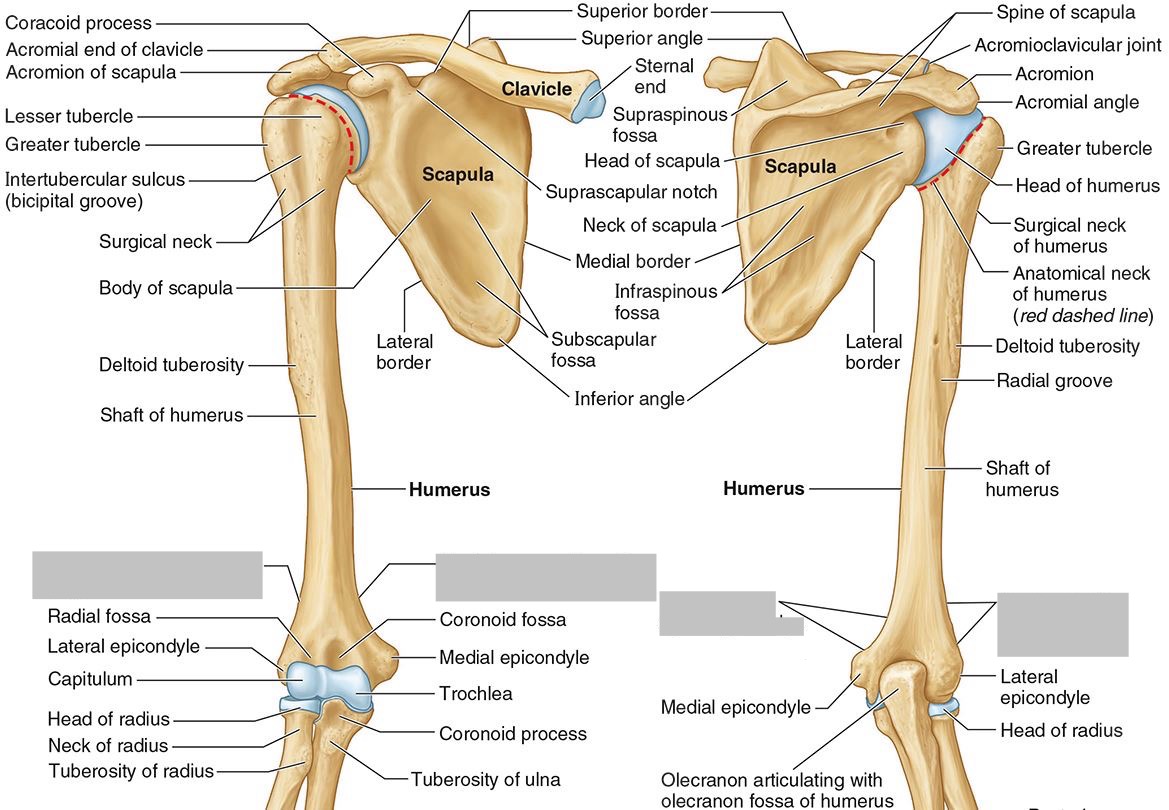

What part of the humerus is this?

The head of the humerus articulates with the scapula at the glenohumeral joint.

What part of the humerus is this?

The anatomic neck is an indentation distal to the head and provides an attachment for the fibrous joint capsule of the glenohumeral joint.

What part of the humerus is this?

The greater tubercle lies lateral and distal to the anatomic neck.

What part of the humerus is this?

The lesser tubercle lies on the anterior/medial side of the humerus, just distal the anatomic neck.

What part of the humerus is this?

The intertubercular (bicipital) groove lies between the greater and lesser tubercles.

What part of the humerus is this?

The surgical neck is a narrow area distal to the tubercles. It is a common site for proximal humerus fractures.

What part of the humerus is this?

The humeral shaft features the deltoid tuberosity laterally for the distal insertion of the deltoid muscle.

What part of the humerus is this?

The radial groove is an oblique depression that contains the radial nerve and deep brachial artery.

Which parts of the humerus is this?

The medial and lateral epicondyles are distal prominences to which many forearm tendons attach, near the elbow joint.

Which parts of the humerus is this?

The medial and lateral supracondylar ridges extend superiorly from the medial and lateral epicondyles.

Which parts of the humerus is this?

The trochlea and the capitulum (the condyles) are the most distal surfaces of the humerus, where it articulates with the forearm bones at the elbow joint

What part of the humerus is this?

The olecranon fossa is a posterior depression above the trochlea that receives that olecranon process of the ulna

What part of the humerus is this?

The coronoid fossa is an anterior depression above the trochlea that receives that coronoid process of the ulna.